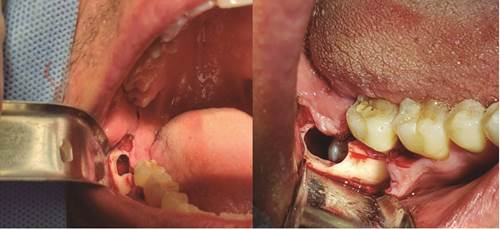

Primero se toma una muestra de la lesión quística (figura 3) y se cementa un botón de resina al diente 4.8. Además, se instala una cánula para descomprimir la lesión. Tras haber controlado al paciente 7 días después, es derivado a la especialidad de ortodoncia para la fijación y tracción del tercer molar (figura 4). La muestra es enviada a biopsia para estudio histopatológico, el cual confirma el diagnóstico de quiste dentígero.